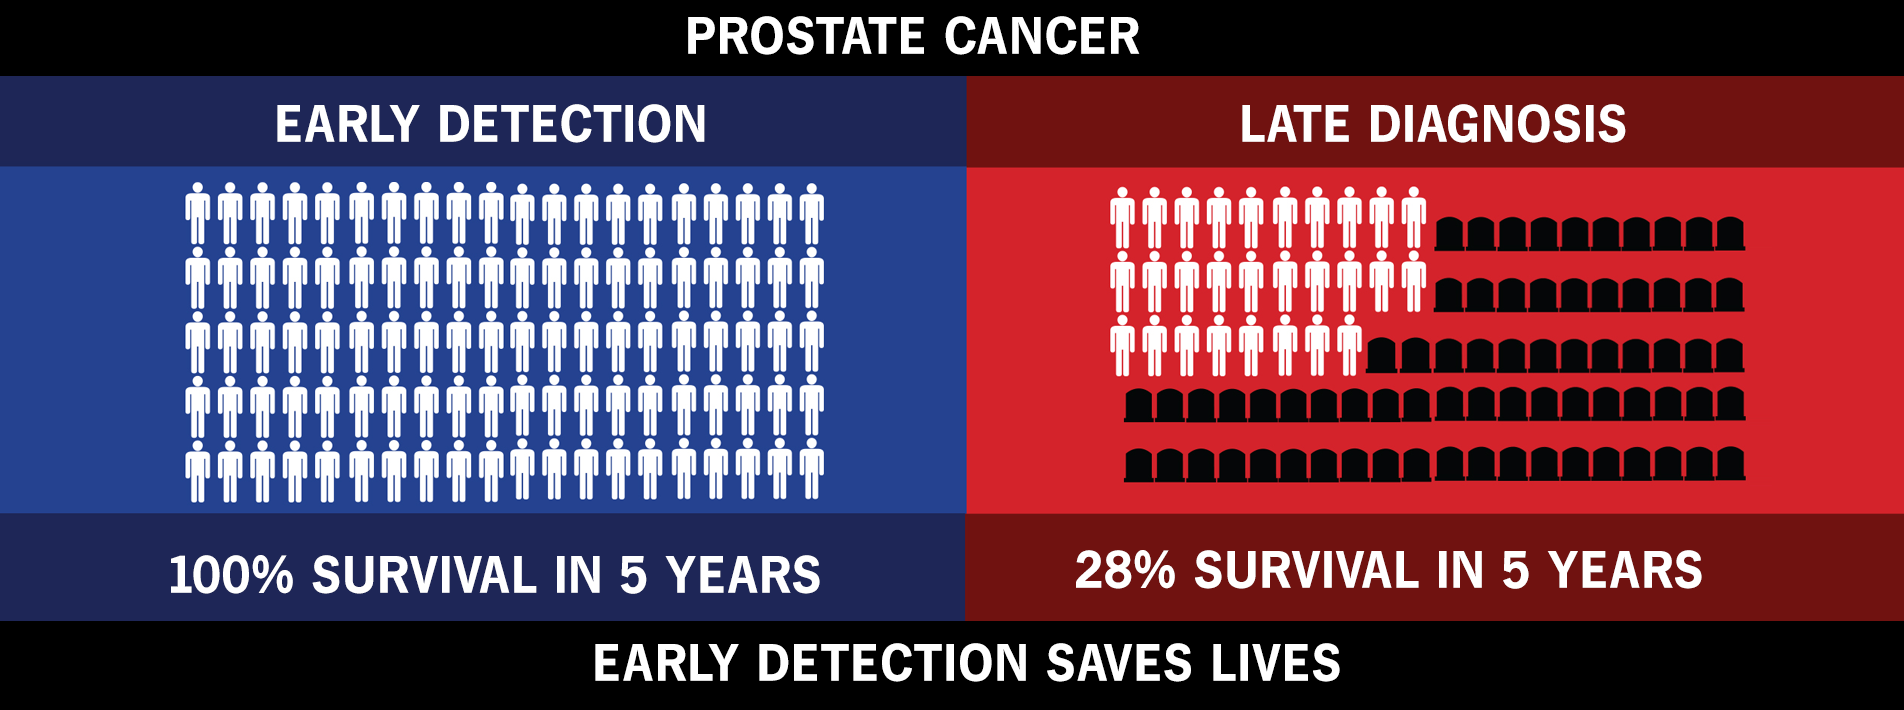

Data That Shows Early Detection Rather Than Late Detection In Breast Cancer